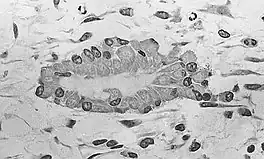

Osteoblasts (purple) rimming a bony spicule (pink - on diagonal of image). In this routinely fixed and decalcified (bone mineral removed) tissue, the osteoblasts have retracted and are separated from each other and from their underlying matrix. In living bone, the cells are linked by tight junctions and gap junctions, and integrated with underlying osteocytes and matrix H&E stain.